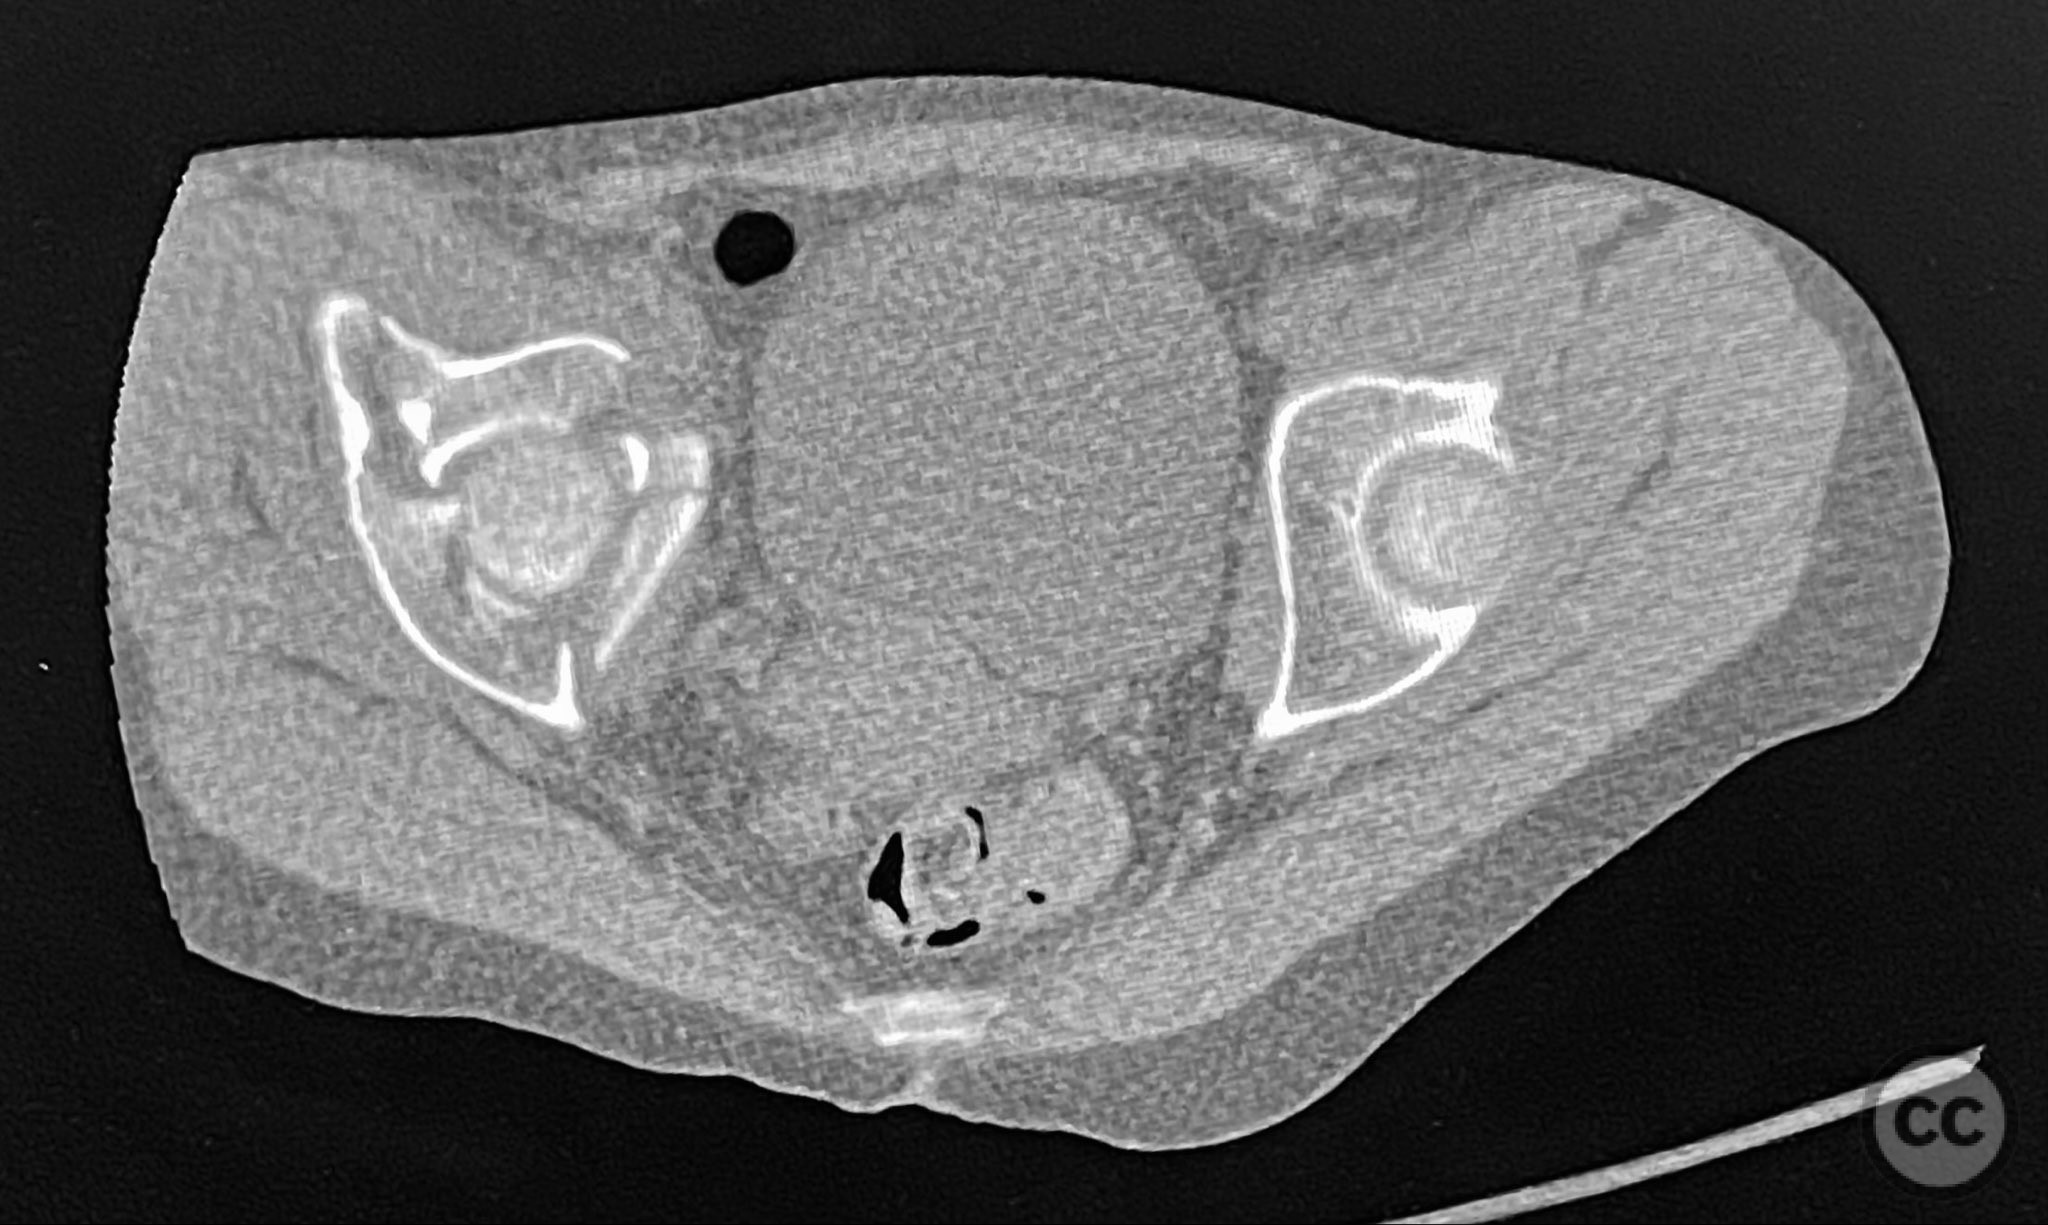

Clinical and radiological findings:  The patient sustained an acetabular fracture with a rare posterior medial dome impaction fragment, as demonstrated on AP pelvic radiographs obtained in skeletal traction. Surface renderings and axial CT images revealed multiple incomplete fracture lines, including a rhomboid-shaped cortical fragment adjacent and proximal to the anterior column/wall fragment. Coronal and sagittal reconstructions further delineated the impacted articular fragment and its relationship to the surrounding acetabular dome. The fracture pattern is classified as AO/OTA 62B3 (associated both-column fracture with dome impaction).

Anatomical surgical approach:  A classical ilioinguinal approach was performed, developing the lateral, middle, and medial windows. The intrapelvic interval was used to access the quadrilateral surface and posterior column. The rhomboid cortical fragment was excised to allow direct visualization and manipulation of the impacted posterior medial dome fragment. Reduction was achieved using a spiked pusher under fluoroscopic guidance. The defect was filled with morselized allograft, and the rhomboid fragment was anatomically reduced. The anterior column was stabilized with a contoured plate. Posterior column reduction was further improved using a reduction clamp applied with one tine lateral to the anterior inferior iliac spine (AIIS) and the other on the quadrilateral surface via the middle window, followed by lag screw fixation.